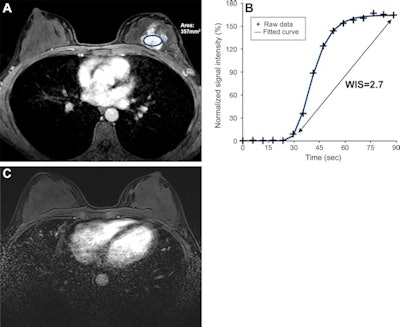

Ultrafast breast DCE-MRI scans in a 47-year-old woman who underwent neoadjuvant chemotherapy for hormone receptor-negative and HER2-positive cancer. (A) Axial last-phase ultrafast T1-enhanced DCE-MRI scan acquired before therapy, with the largest region of interest placed over the lesion (oval); (B) wash-in slope on the initial ultrafast time-signal intensity curve of the breast cancer; and (C) axial postcontrast T1-enhanced standard DCE-MRI scan acquired after therapy. The tumor manifested as a 4-cm nonmass enhancement in the left breast. The time-signal intensity curve at initial ultrafast DCE-MRI shows a high wash-in slope of 2.7% per second. A DCE-MRI scan acquired after therapy showed no residual enhancement, and histopathologic examination revealed no invasive residual cancer. Images courtesy of RSNA.

Ultrafast breast DCE-MRI scans in a 47-year-old woman who underwent neoadjuvant chemotherapy for hormone receptor-negative and HER2-positive cancer. (A) Axial last-phase ultrafast T1-enhanced DCE-MRI scan acquired before therapy, with the largest region of interest placed over the lesion (oval); (B) wash-in slope on the initial ultrafast time-signal intensity curve of the breast cancer; and (C) axial postcontrast T1-enhanced standard DCE-MRI scan acquired after therapy. The tumor manifested as a 4-cm nonmass enhancement in the left breast. The time-signal intensity curve at initial ultrafast DCE-MRI shows a high wash-in slope of 2.7% per second. A DCE-MRI scan acquired after therapy showed no residual enhancement, and histopathologic examination revealed no invasive residual cancer. Images courtesy of RSNA.They looked at prospective data from 50 women with an average age of 49 years. Out of these, 20 achieved pathologic complete response, while 25 had residual cancer burden.